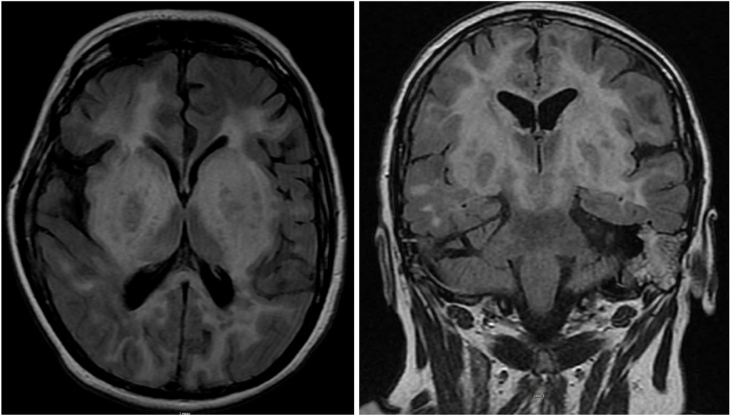

Encephalopathy was initially thought to be of a toxic metabolic cause secondary to sepsis due to pneumonia diagnosed by imaging. Thus, the patient was started on cefepime and vancomycin; continuous EEG monitoring was done but did not show any seizure activity and her antiepileptic medication dosing was adjusted. However, patient’s mental status remained unchanged and therefore, MRI brain with contrast followed by lumbar puncture (LP) was pursued. MRI showed symmetric marked edema involving the bilateral basal ganglia with mass effect on lateral ventricles (Figs. 1 and 2). Cerebrospinal fluid (CSF) analysis demonstrated lymphocytic pleocytosis 95 cells/uL, low CSF glucose of 29 mg/dL and high protein of 103.1 mg/dL consistent with viral encephalitis. Due to remote history of natalizumab treatment, JC virus testing was sent in addition to other viral studies, which returned as negative. However, final viral PCR result was positive for herpes encephalitis type 2 with 19980 viral copies. The patient was started on treatment with intravenous acyclovir with subsequent improvement in mental status and was eventually discharged to a rehabilitation center.

Figs. 1 and 2.

MRI brain with contrast showing marked edema as well as enhancement in the bilateral basal ganglia, frontal, parietal, occipital lobes and brainstem.